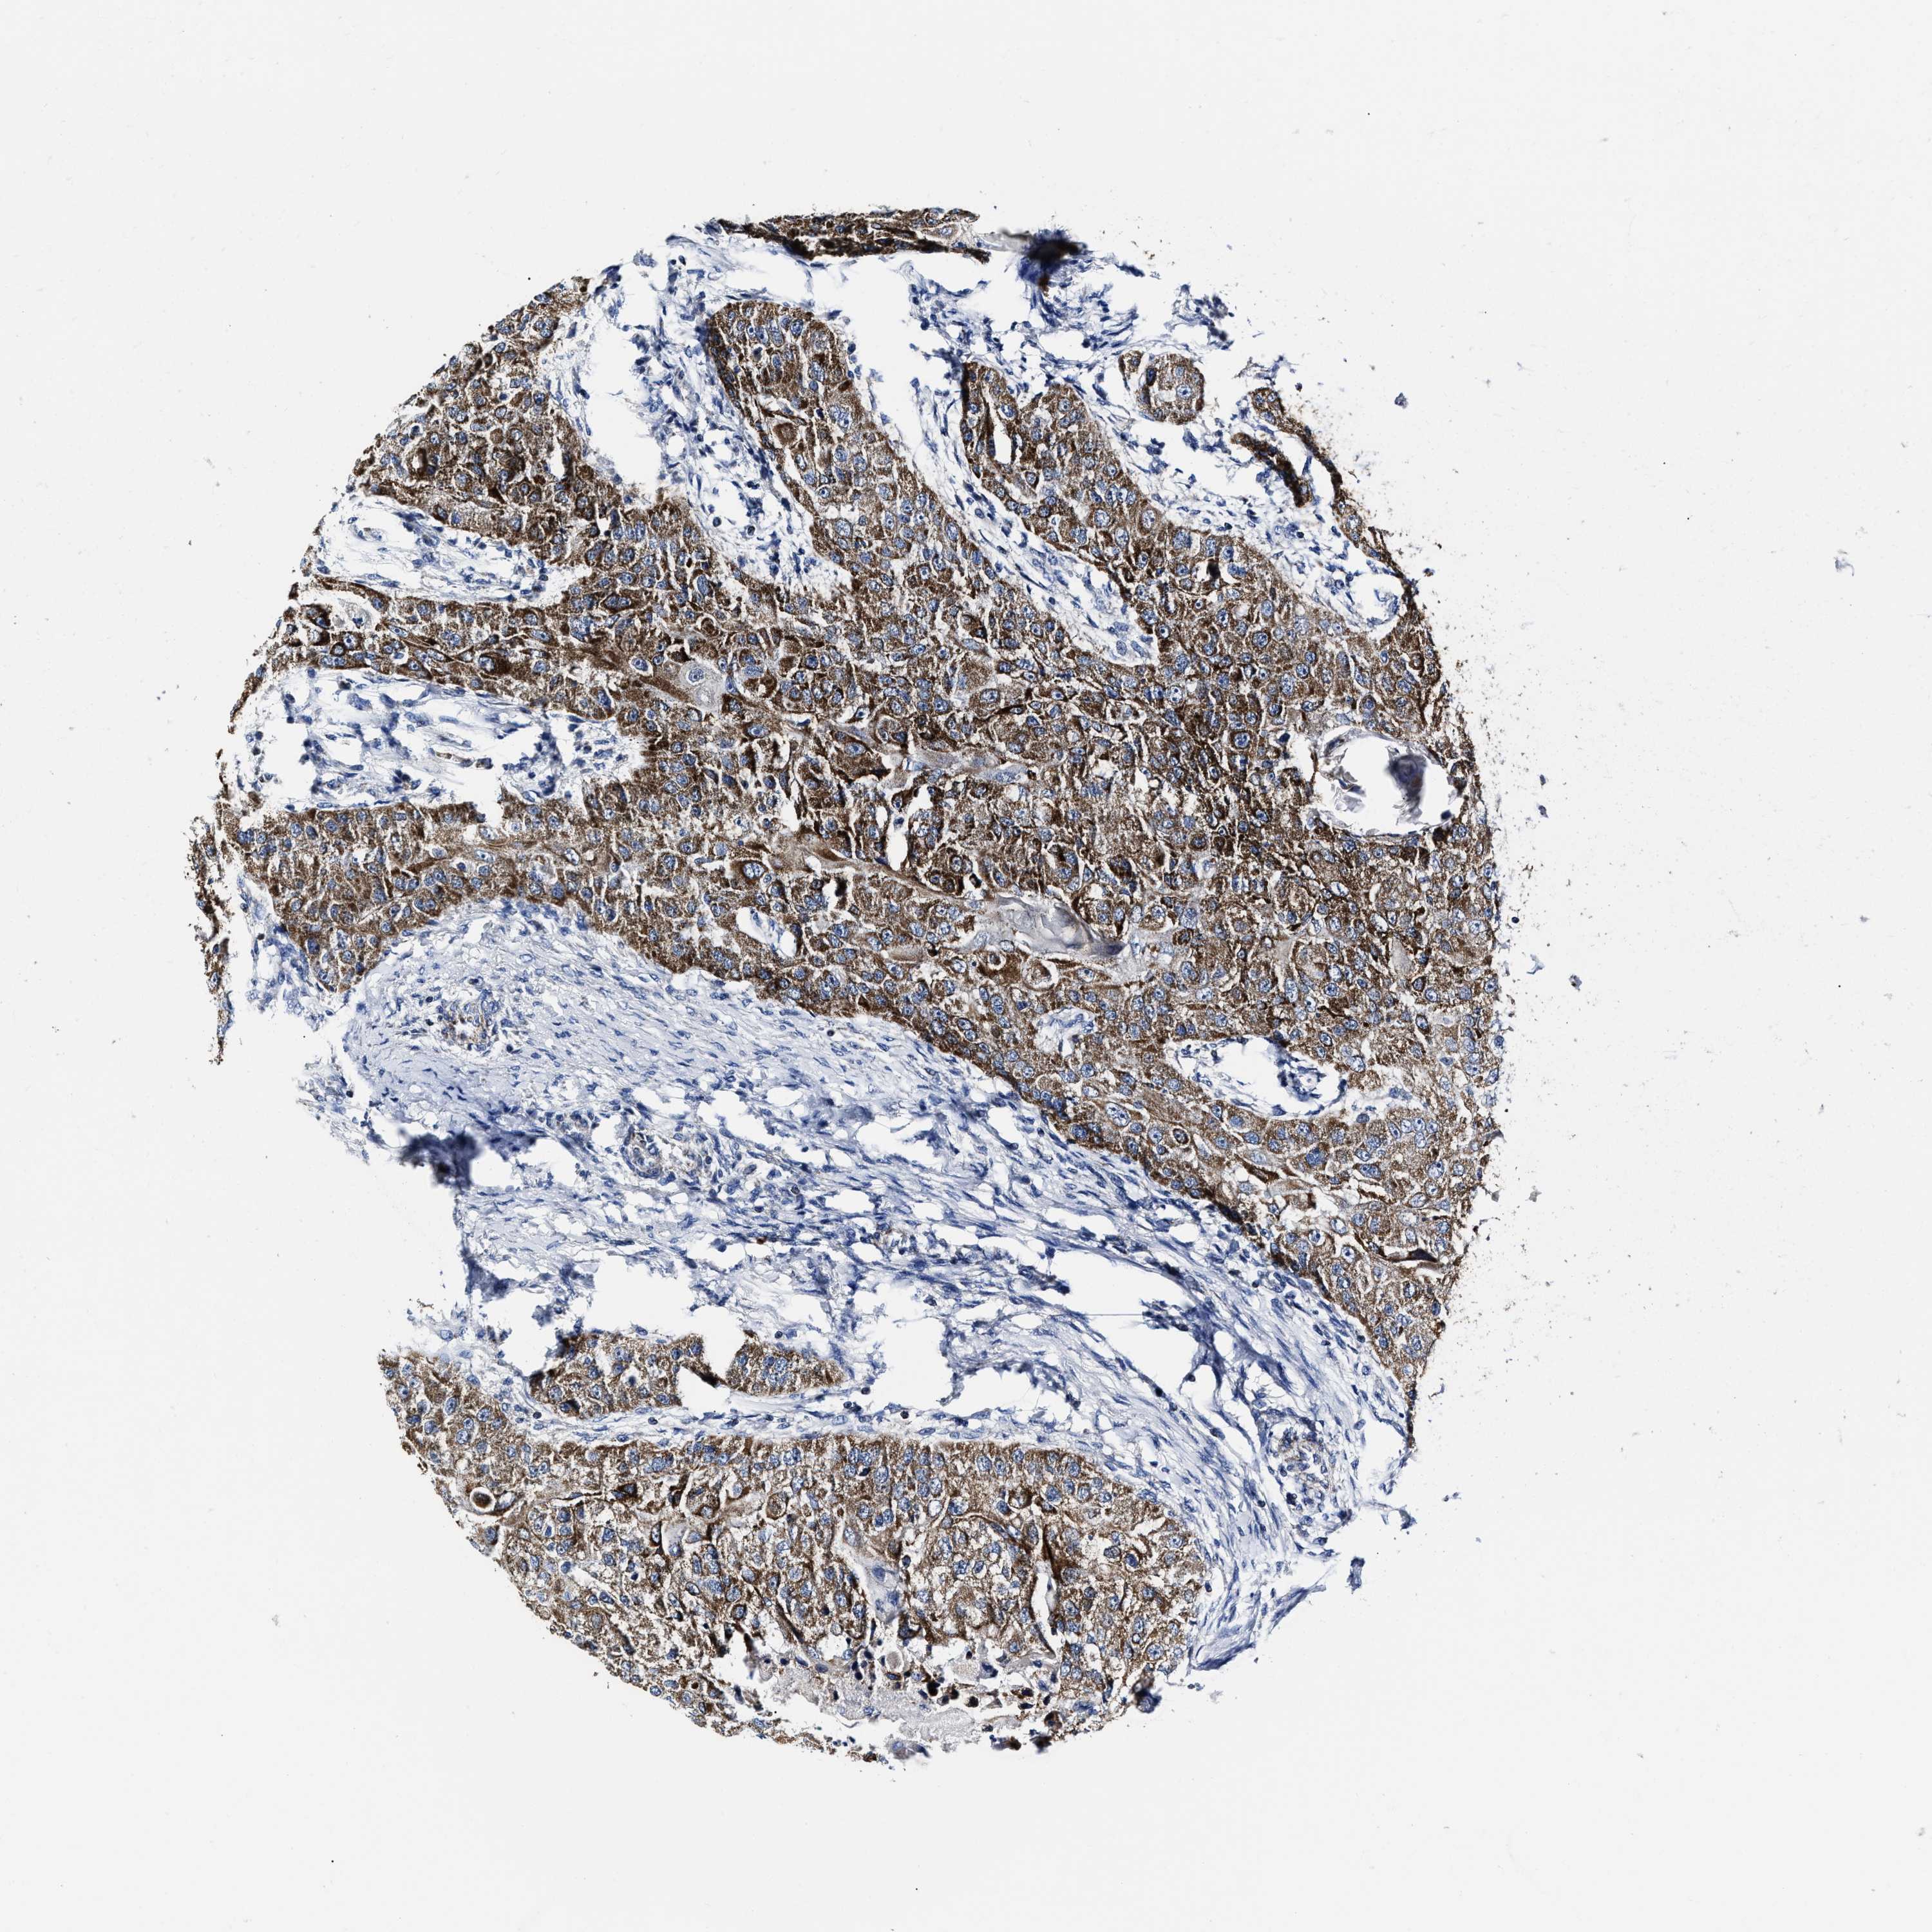

HEAD AND NECK CANCER - Protein expressioni

A mouse-over function shows sample information and annotation data. Click on an image to view it in a full screen mode. Samples can be filtered based on level of antibody staining by selecting one or several of the following categories: high, medium, low and not detected. The assay and annotation is described here.

Antibody stainingi

Antibody staining in the annotated cell types in the current human tissue is reported as not detected, low, medium, or high, based on conventional immunohistochemistry profiling in selected tissues. This score is based on the combination of the staining intensity and fraction of stained cells.

Each image is clickable and will lead to virtual microscopy that enables deeper exploration of all samples and also displays staining intensity scores, fraction scores and subcellular localization as well as patient and tissue information for each sample.

Antibody HPA059109

Staining

High

Medium

Low

Not detected

Intensity

Strong

Moderate

Weak

Negative

Quantity

>75%

75%-25%

<25%

None

Location

Nuclear

Cytoplasmic/membranous

Cytoplasmic/membranous,nuclear

Squamous cell carcinoma, NOS

Squamous cell carcinoma, metastatic, NOS

Adenocarcinoma, NOS